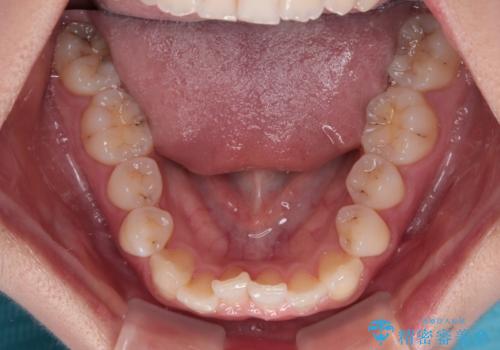

- 上顎前歯のクロスバイトを気にして来院された患者様です。

ワイヤー矯正でもマウスピース矯正でも対応可能でしたが、マウスピースによる自己管理に一切の自信がないとのことで、ワイヤー装置にて矯正治療を行うこととしました。